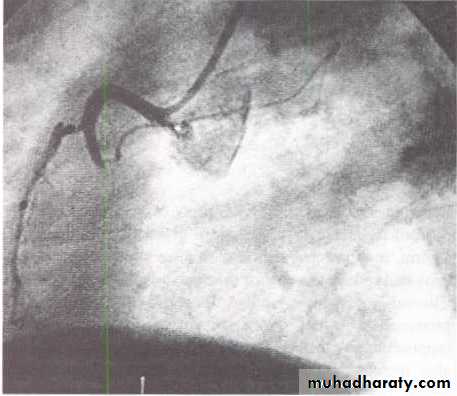

Percutaneous coronary intervention PCI.

Primary percutaneous coronary intervention (PCI).Thrombolysis.